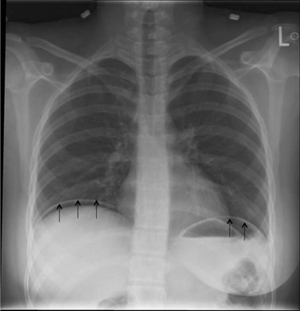

Large bowel obstruction (Cecal volvulus; black arrows).

Large bowel obstruction (Cecal volvulus; black arrows). Free intra-abdominal air below the diaphragm.